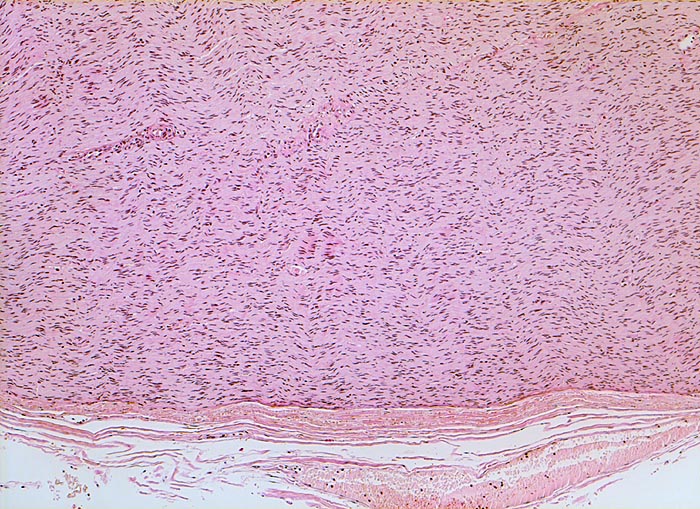

PathoPic – image database / PathoPic ID 5275 - peripherer Nerv (Intercostalnerv)

peripherer Nerv (Intercostalnerv)

Normalbefund

Nerv peripher

Nervensystem

Schwannzellen mit langgezogenen Kernen in welliger Anordnung kennzeichnen den peripheren Nerven. Der Nerv ist umgeben vom Perineurium aus Bindegewebe und Gefässen.

Intercostalnerv

Histologie

50